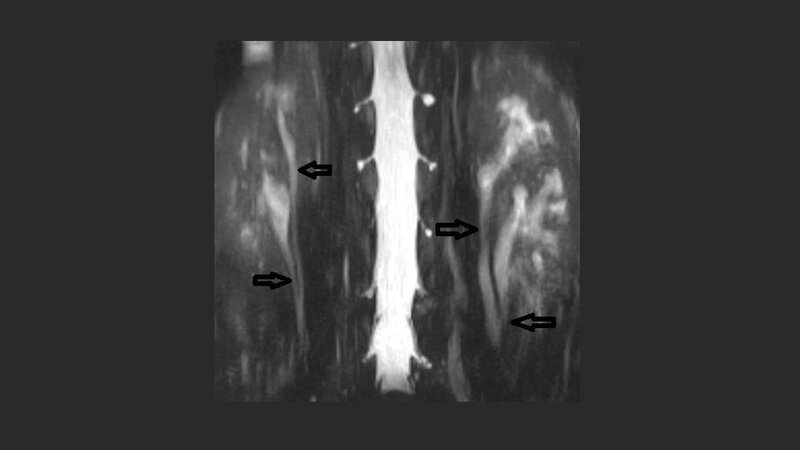

Anomalien und Normvarianten – Interne Veränderungen 2.11: Ureter fissus

Schlüsselwörter: CT, MRT, Ureter fissus